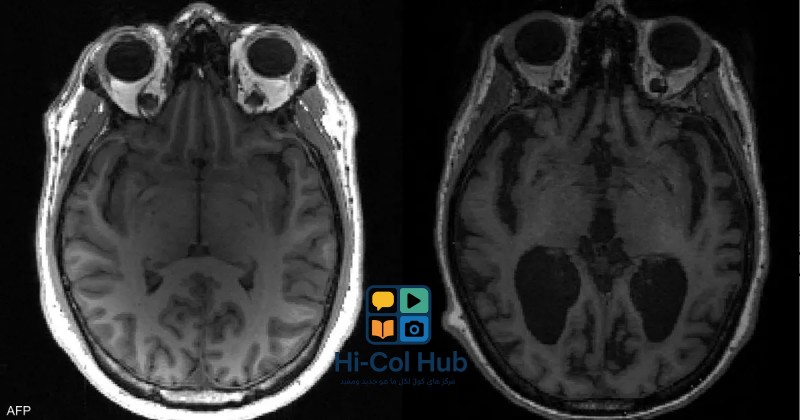

يلعب البحث العلمي دورًا حاسمًا في فهم أمراض الدماغ وتطوير علاجات فعالة. من خلال دراسة الآليات البيولوجية المعقدة التي تكمن وراء هذه الأمراض، يمكن للعلماء تحديد أهداف علاجية جديدة وتطوير أدوية وتقنيات مبتكرة. على سبيل المثال، أدت الأبحاث الحديثة في مجال علم الوراثة إلى تحديد العديد من الجينات المرتبطة بأمراض الدماغ، مما فتح الباب أمام تطوير علاجات جينية تستهدف هذه الجينات بشكل مباشر. كما أن الأبحاث في مجال الخلايا الجذعية تحمل وعودًا كبيرة في إصلاح الأنسجة العصبية التالفة واستعادة وظائف الدماغ المفقودة. بالإضافة إلى ذلك، فإن الأبحاث في مجال الذكاء الاصطناعي وتقنيات التصوير العصبي تساعد على تطوير أدوات تشخيصية أكثر دقة وفعالية، مما يسمح بالكشف المبكر عن أمراض الدماغ وتوجيه العلاج بشكل أفضل. يجب على الحكومات والمؤسسات البحثية والجهات المانحة الاستثمار في البحث العلمي في مجال أمراض الدماغ، وتشجيع التعاون بين العلماء والباحثين من مختلف التخصصات، من أجل تسريع وتيرة الاكتشافات العلمية وتطوير علاجات جديدة.